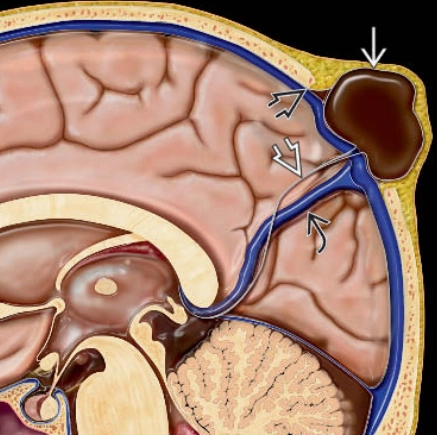

• Thoát vị não-màng não đỉnh dạng thoái triển (Atretic parietal cephaloceles)

Thoát vị não-màng não đỉnh dạng thoái triển (Atretic parietal cephaloceles)

• Thoát vị màng não thoái triển thai nhi (Atretic cephalocele)